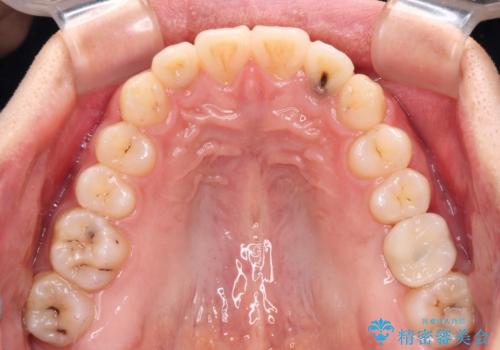

- 前歯のクロスバイトと、大学生のころから放置している虫歯を気にして来院された患者様です。

マウスピースでの矯正治療を希望されていましたが、前歯のクロスバイトは不十分な仕上がりや歯髄壊死などのリスクが高くなるため、術前にワイヤーで大まかに整えてからインビザラインにて矯正治療を行うこととしました。

奥歯の虫歯は抜歯が必要であったので、矯正治療前に抜歯をし、矯正治療と並行してインプラントによる補綴治療を行うこととしました。